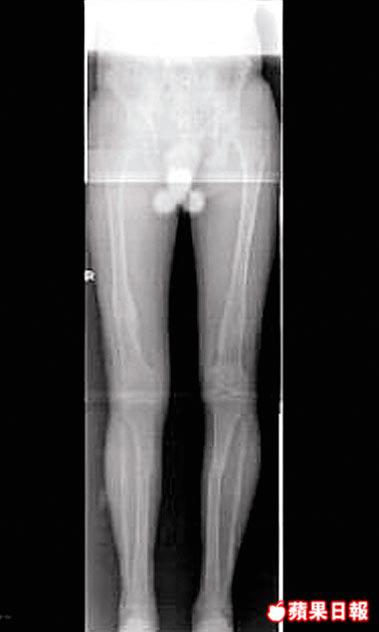

周宏表示,拉骨手術要先切開所需延長的骨骼,例如大腿或脛骨(俗稱小腿粗骨),部份病人兩節骨也要拉長,待七日後在骨骼插入鋼釘,並在兩條腿中間連接體外固定支架,再接駁延長器,再每日調校延長器令骨骼拉長一毫米,因骨骼延長太快會難以癒合,並會影響血管及神經,每日需分四次調校延長器;病人每天要接受物理治療,刺激筋腱及肌肉隨骨骼生長,否則關節會變形,「拉骨冇知覺,但拉筋會好痛。」

病人使用延長器平均8個月,共增高1.3吋至8.1吋不等,每節骨骼平均延長2.08吋。增高最多是一名11歲侏儒症病人,但要先後做了三次拉骨手術,有病人出現短暫併發症,如鋼釘位置發炎、關節活動幅度減少等,有關研究結果已在新一期《香港醫學雜誌》刊登。